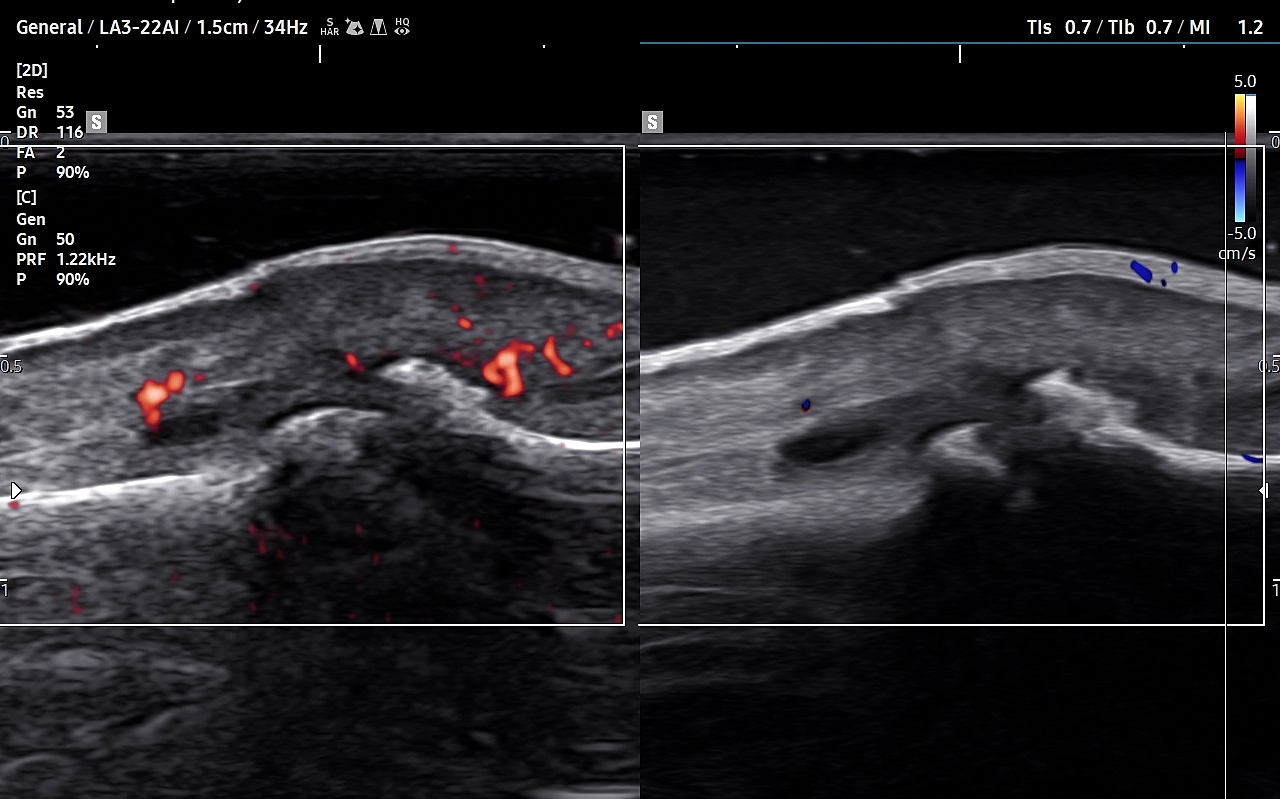

USG stawu kolanowego

Badanie USG stawu kolanowego ma duże znaczenie w diagnostyce chorób kolan u młodszych i starszych dzieci. Wynika to faktu, iż w tych grupach wiekowych nieskostniała rzepka umożliwia penetrację fal ultradźwiękowych w głąb kolana oraz z charakteru typowych dla dzieciństwa urazów (np. kolano skoczka, choroba Osgood-Schlattera). U dorosłych z kolei USG stawu kolanowego ma ważne zastosowanie przy ocenie przeciążeń, urazów, zapaleń i zwyrodnień zewnętrznych tkanek miękkich stawu, jak np. patologie kaletek, więzadeł pobocznych, czy przyczepów mięśniowych; a także ograniczone zastosowanie w ocenie schorzeń wewnątrzstawowych, takich jak zapalenie i przerost maziówki, uszkodzenia chrząstek szklistych powierzchni stawowych, czy torbiel Bakera.